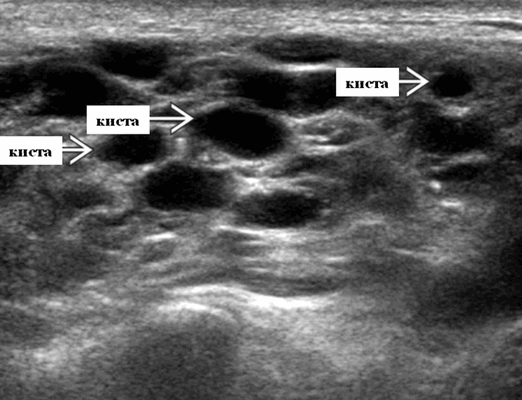

- Лимфома лимфоидной ткани, ассоциированная со слизистой оболочкой (MALT-лимфома): диффузная, неоднородная эхо-картина, нечеткие, гипоэхогенные, похожие на опухоль участки. На момент пункции под контролем УЗИ имеется внутрикистозная или паренхиматозная кальцификация из-за конечной стадии воспалительного изменения. Небольшие кистозные области возникают вследствие сдавления терминальных протоков лимфоидной гипертрофией. Множественные небольшие гипоэхогенные области (которые, как считается, представляют собой лимфоидные агрегаты) разбросаны на фоне ткани слюнной железы. Диффузная железистая гиперваскуляризация. Имитирует диагноз хронический сиаладенит, который часто ставится при биопсии.

Серошкальное УЗИ. Узловая НХЛ. Одиночные или множественные увеличенные яйцевидные внутрипаротидные лимфатические узлы. Гомогенно гипоэхогенный по отношению к паренхиме околоушной железы. Сетчатый эхосигнал. Заднее акустическое усиление. Первичная паренхиматозная НХЛ. Рассеянный, неоднородный эхосигнал; нечеткие, гипоэхогенные, похожие на опухоль участки. В пунктате внутрикистозная или паренхиматозная кальцификация из-за конечной стадии воспалительного изменения. Небольшие кистозные области образуются из-за сдавления терминальных протоков лимфоидной гипертрофией. Множественные небольшие гипоэхогенные участки (представляют собой лимфоидные агрегаты), разбросанные на фоне ткани слюнной железы. Изменения могут имитировать хронический сиалоаденит и диагноз часто ставится при биопсии. На УЗИ необходимо искать аналогичное поражение других слюнных и слезных желез, фон синдром Шегрена, BLEL. Может иметь или не иметь перипаротидную и шейную лимфаденопатию

- Серошкальное УЗИ. Спектр сонографических находок от простых кист до смешанных и солидных образований. Кистозные, смешанные и солидные поражения могут возникать одновременно в околоушных железах. Кистозные поражения (кисты ДЛК). Хорошо очерченная киста, разного размера, от анэхогенной до гипоэхогенной структуры с задним акустическим усилением. Сеть тонких перегородок ± муральные узлы. Часто встречаются внутренние эхо, которые могут быть мобильными. Сотовидная внешность паренхимы околоушной железы, когда она диффузно изменена з а счет кист. Смешанные поражения (ДЛП). Границы могут быть плохо очерченными, разного размера. Структура преимущественно гипоэхогенная, железы могут быть неоднородными. Без заднего акустического усиления. Солидные поражения (околоушная лимфаденопатия). Множественные овальные / круглые, гипоэхогенные, внутрипаротидные лимфоузлы на УЗИ. Четкий корковый слой ± сохранная корневая архитектура. Сопутствующая реактивная шейная лимфаденопатия